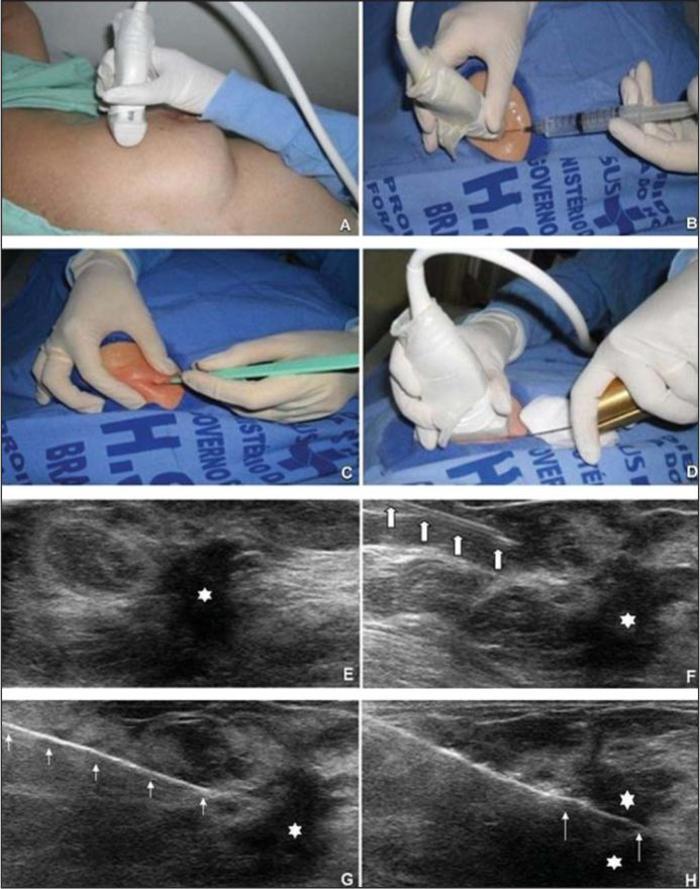

超声引导下乳腺肿块穿刺活检一例

图片尺寸1080x1440